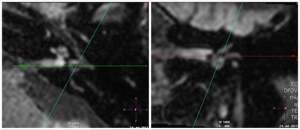

MRI imaging of the inner ear

Superior semicircular canal Lateral semicircular canal  Lateral semicircular canal  Utricle Vestibule